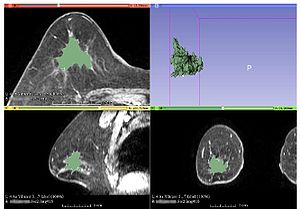

- 3.46 Role of Mri-Based Tumor Volume Measurements in Surgical Treatment of Breast Cancer